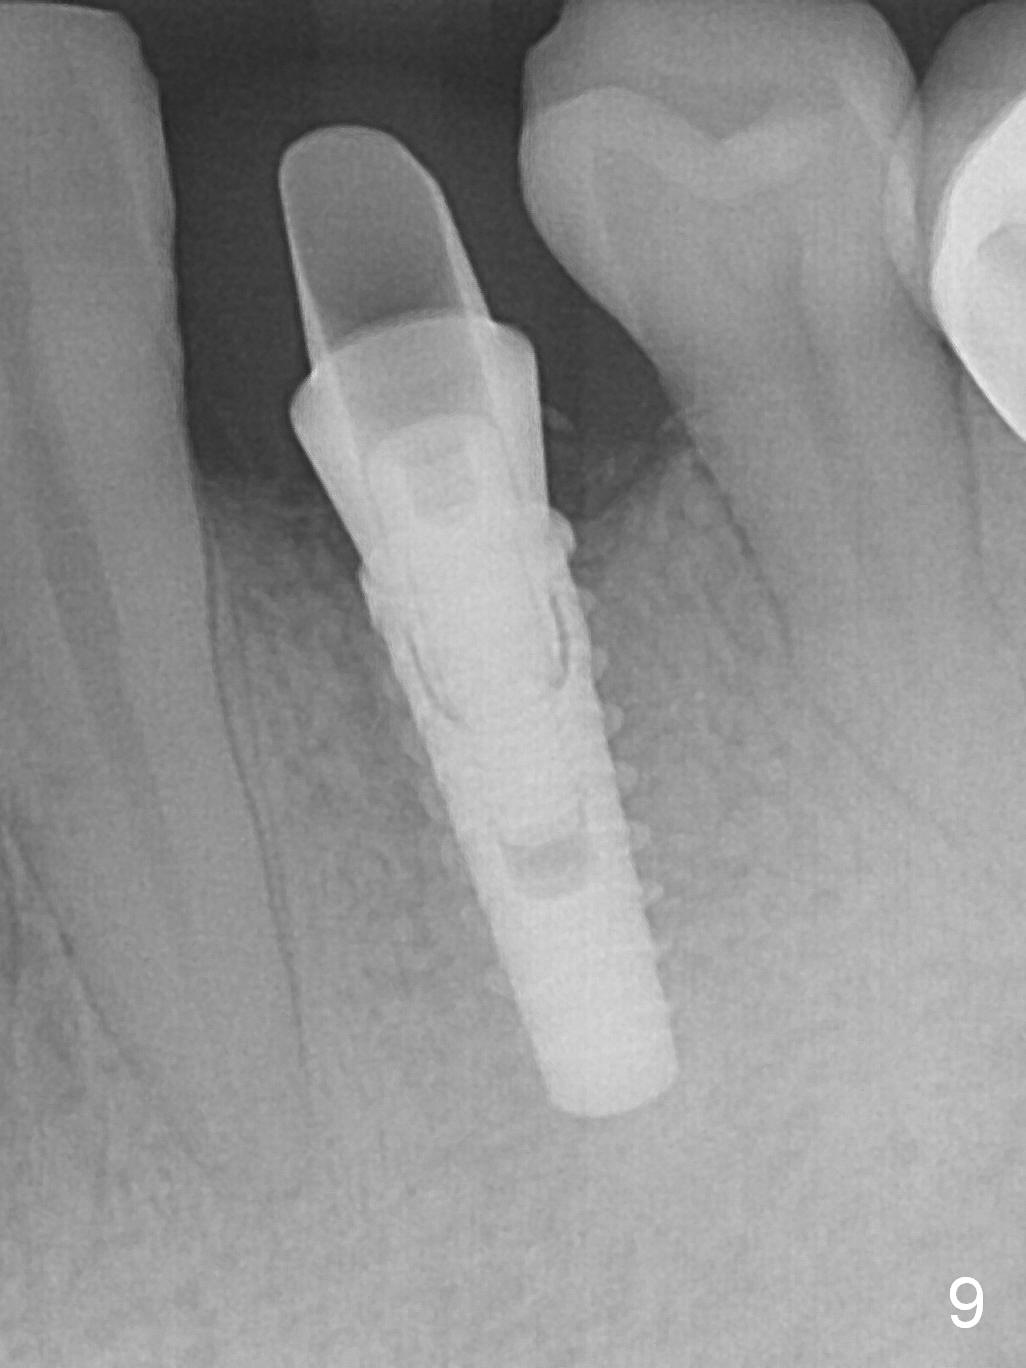

The implant seems to have osteointegrated 4 months postop (Fig.9). When a permanent crown is fabricated, it should have normal occlusal and buccal contour (from Fig.11 (provisional) to 12 red and black curved lines) as well as the buccal cervical extension (Fig.12 to cover the buccal gingiva (Fig.10 *). If the lingual margin of the abutment is too prominent, return the case and the abutment will be changed to the one with 2 mm cuff (existing 3 mm). The lingual margin of the abutment will be trimmed. The patient is not pleased with the short buccal margin of the crown after cementation (Fig.13). In fact the provisional should have been fabricated so that the its buccal margin should be subgingival and within the gingival outline. It may prevent buccal plate collapse. In fact the crown dislodges 1 year post cementation. The lingual margin is prep lower to increase the abutment height. Impression is taken. Although the access hole is unnecessary for cementation, it acts as an escape hole so that there is no excess cement cervically (Fig.14-18).